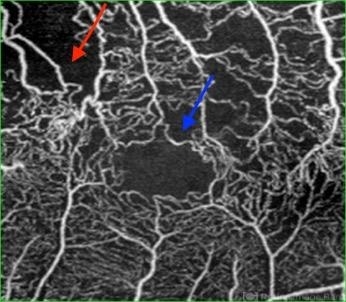

- OCTA image in a case of BRVO highlighting the capillary non perfusion areas related to the superior branch retinal vein occlusion.